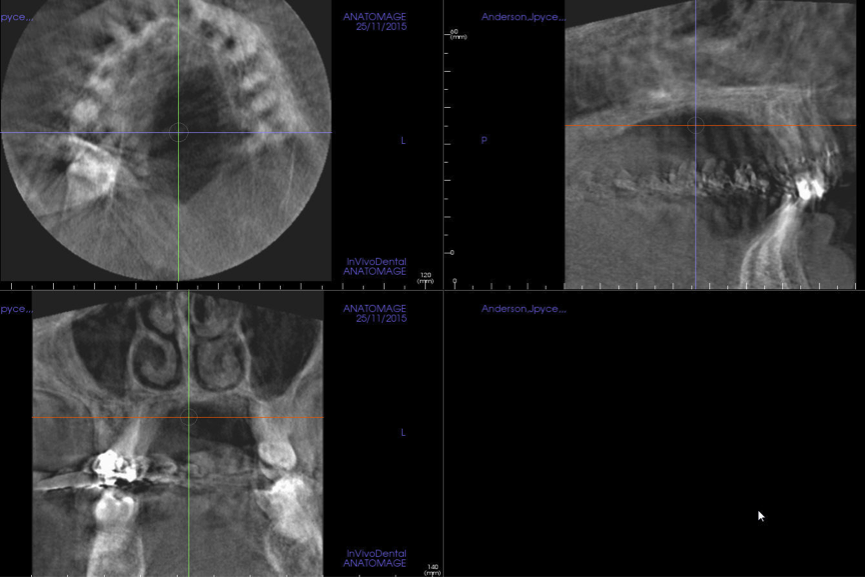

5. Analyze All Available Images with the Proper Diagnostic Utilities

After all of the available diagnostic information is collected, the area of interest is assessed from all perspectives in order to correlate the reported or observed clinical findings to possible changes in the radiologic appearance of the hard tissues in the affected site. This includes a comparison of the region with the contralateral side to evaluate for possible asymmetry or unilateral irregularities of the anatomical structures; altered appearance of known tissues/structures; possible alteration, discontinuity, or even destruction of osseous boundaries; possible shape changes in known anatomical structures; possible mass development and features of the developing mass; possible effects of a mass on known anatomical structures and boundaries; and more (Figure 5). An accurate description of the entity under investigation will reveal useful information about the tissue of origin, its structure (ie, hollowed, cystic, or solid), and its nature (fast growing/aggressive or slow growing/subtle). In the end, a list containing all collected radiologic data should be compiled and used to create a differential diagnostic list consisting of all possible pathological entities that fit the collected descriptive data.

(5.) Sagittal orthogonal section of the maxillary midline showing a developing mass in the posterior pharyngeal wall. This is posterior pharyngeal tonsilar hypertrophy (hypertrophic ad- enoids), which is causing significant narrowing of the airway at the level of the naso-pharynx.

Figure 5